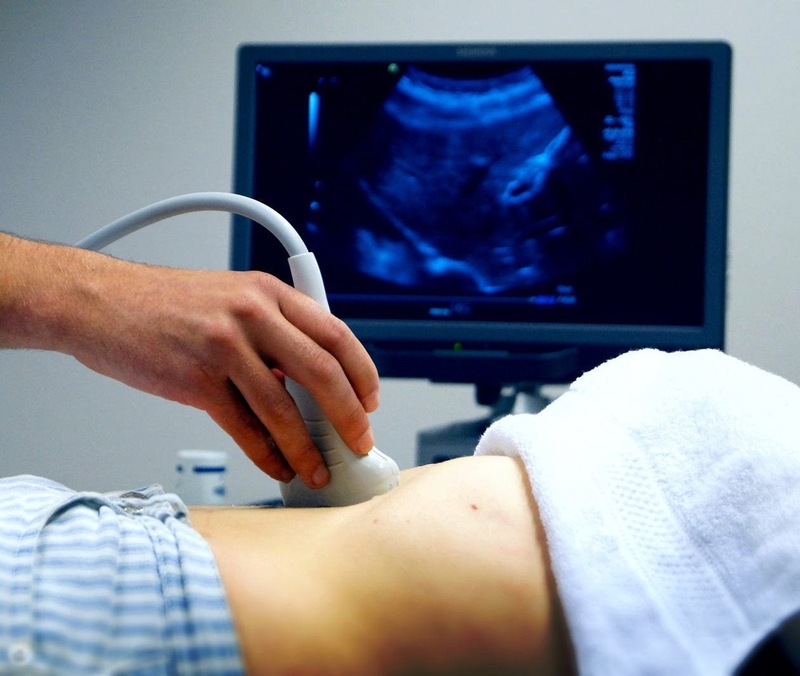

Từ tuần thai thứ 32 đến 36, bác sĩ sản khoa sẽ dùng phương pháp siêu âm thai để theo dõi tử cung, kiểm tra vị trí bám của bánh rau. Rau thai bám mặt trước được đánh giá là an toàn nếu bánh rau trở về đúng vị trí ở giai đoạn cuối thai kỳ. Nếu từ tuần 33 đến 34, nhau thai không di chuyển lên trên mà vẫn bám thấp ở tử cung thì sẽ dẫn đến tình trạng nhau tiền đạo. Trong trường hợp này, bác sĩ sẽ siêu âm nhằm xác định lại vị trí em bé, bánh nhau và mẹ sẽ có thể được chỉ định sinh mổ.